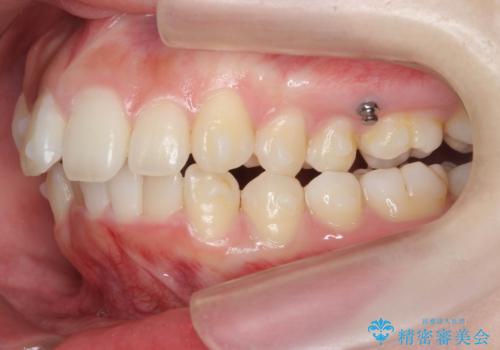

口腔内の清掃状態の良さに加えて、マウスピースを毎日きっちりと装着し、しっかりと使用していただけたことからワイヤー矯正は行わずにきれいに歯並びを治すことができました。

途中顎位が変わり、マイクロインプラントを併用した上顎臼歯の遠心移動が必要となったため治療が長期化しました。